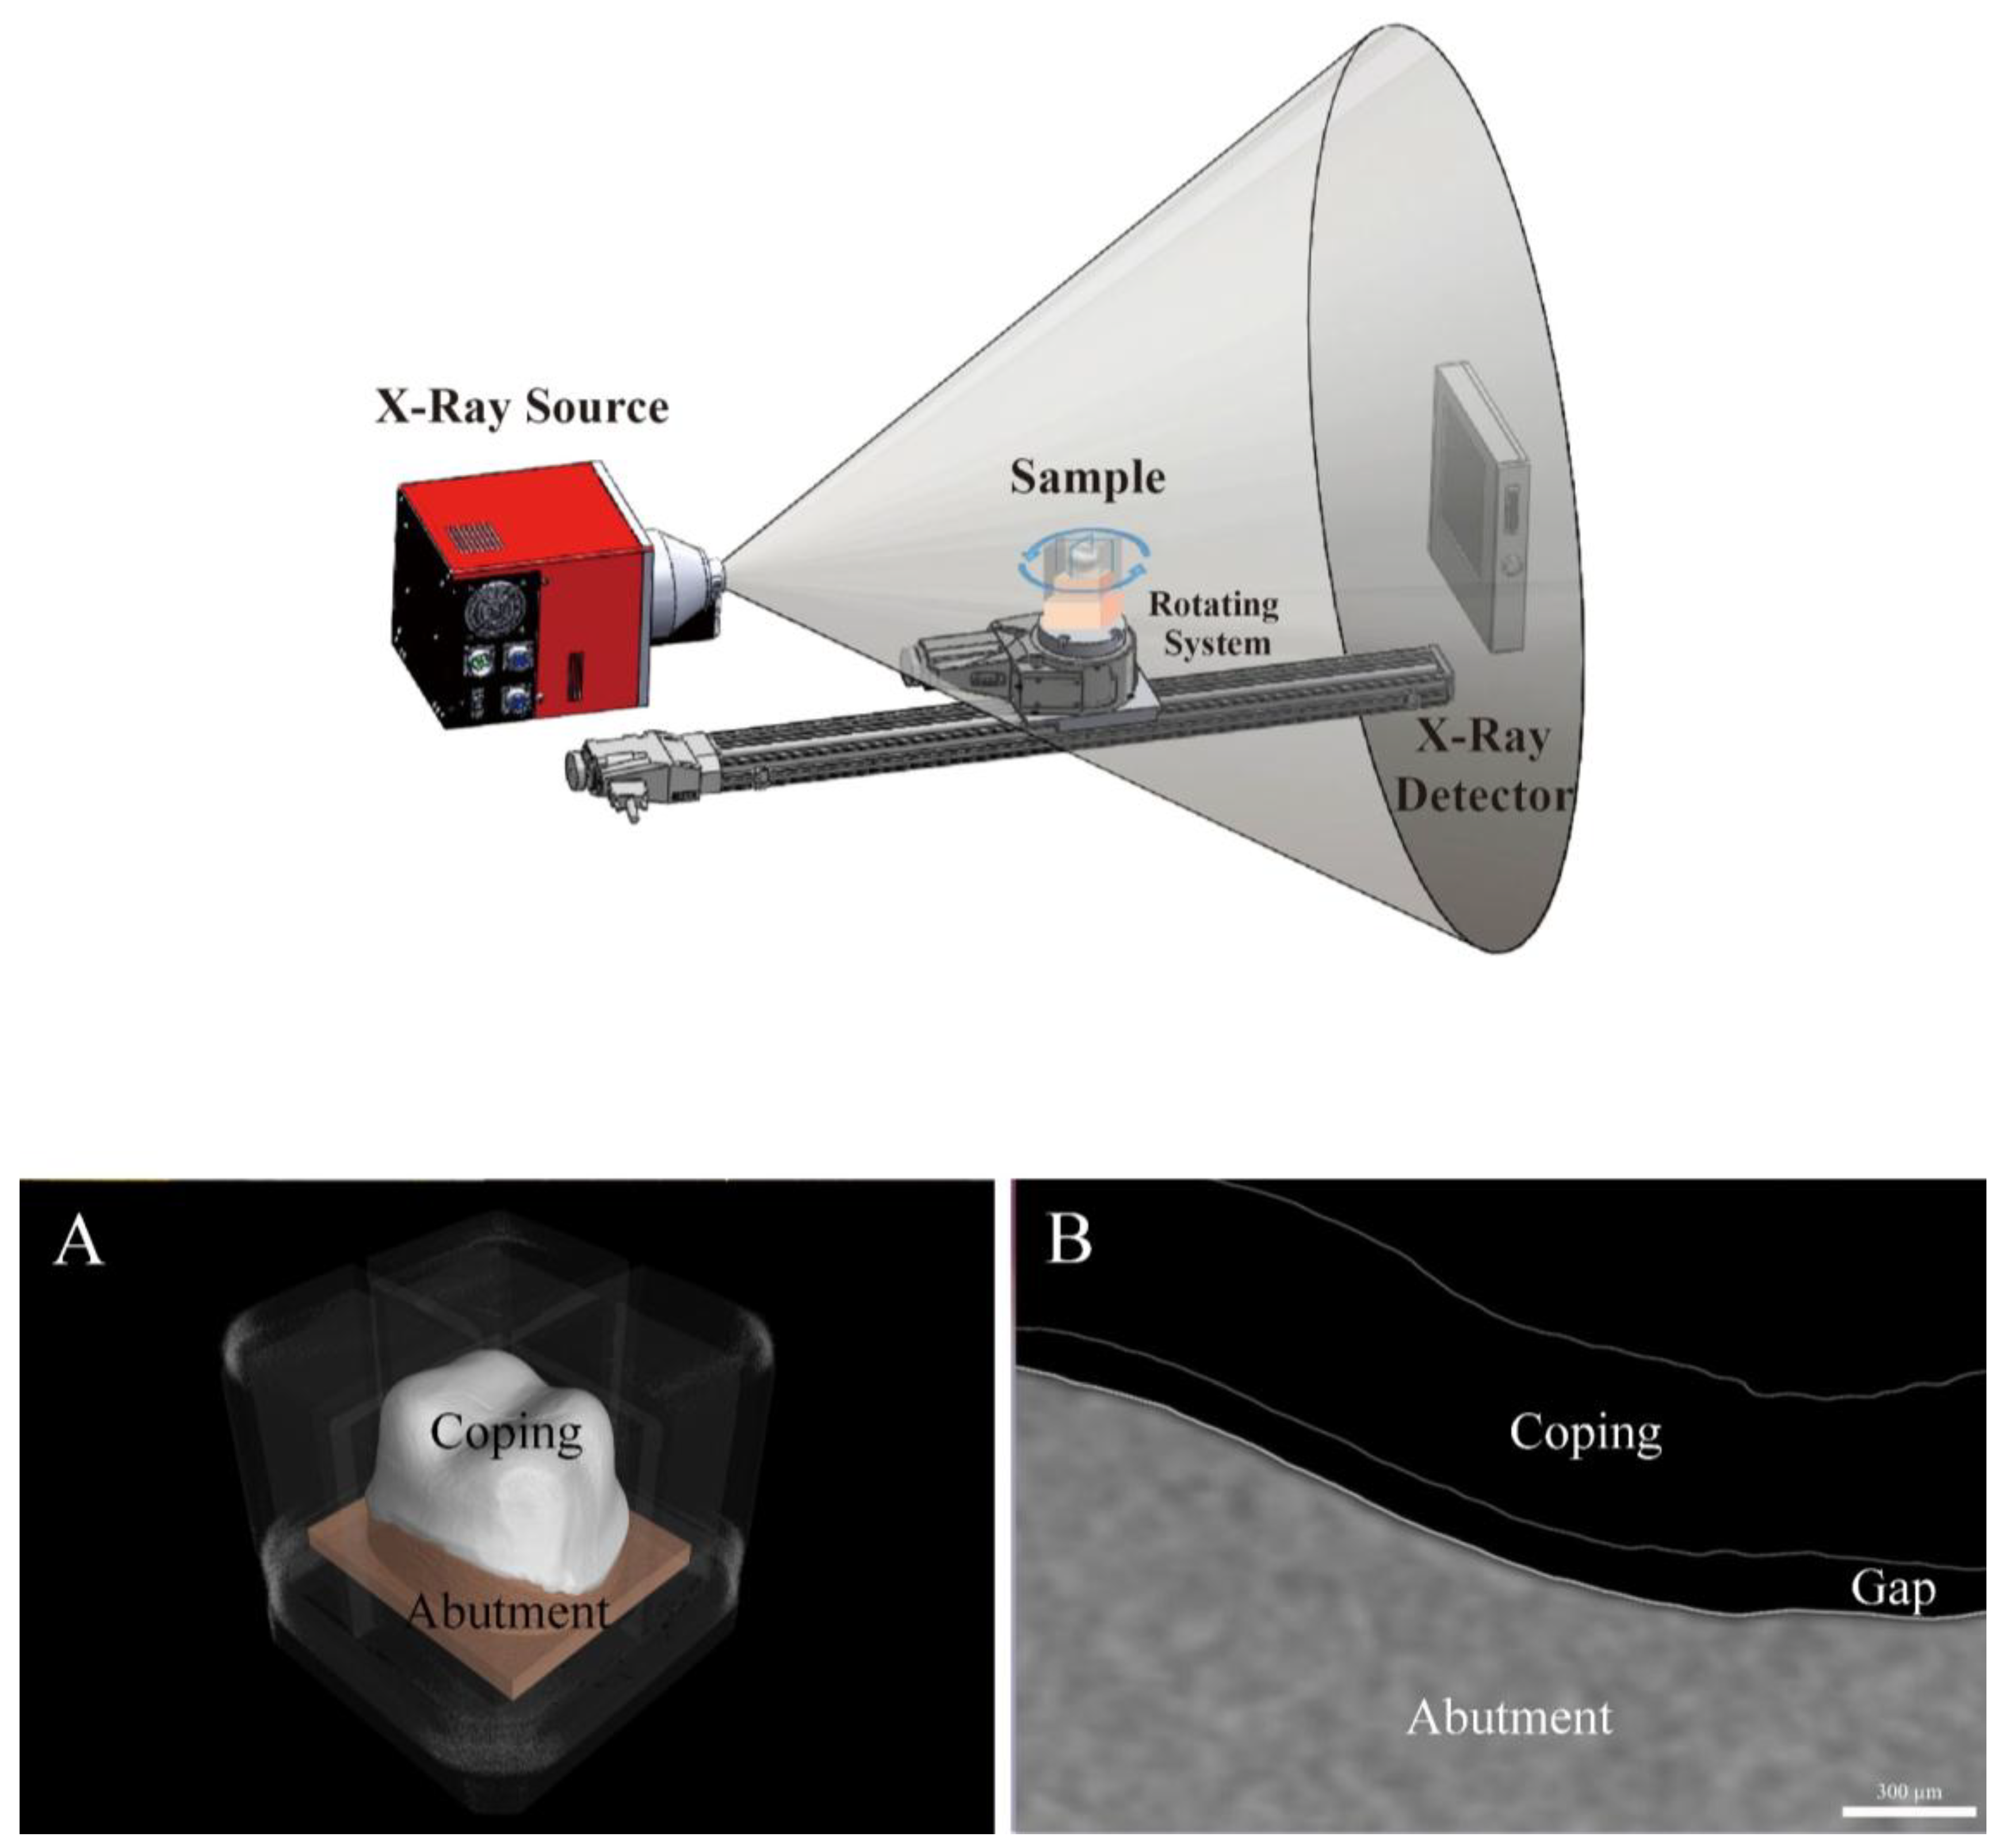

- Micro-computed tomography (MCT): MCT measures the internal and marginal fit of the prosthesis using radiography. The merits of this method include a high resolution and the ability to measure the desired parts by obtaining 3D images. However, the disadvantages of this method include the difficulty to measure metallic prostheses due to the presence of artifacts and an increased risk of exposure to radiation [3,4,13,14,15,21,36].

2.2.4. Micro-Computed Tomography (MCT Group)